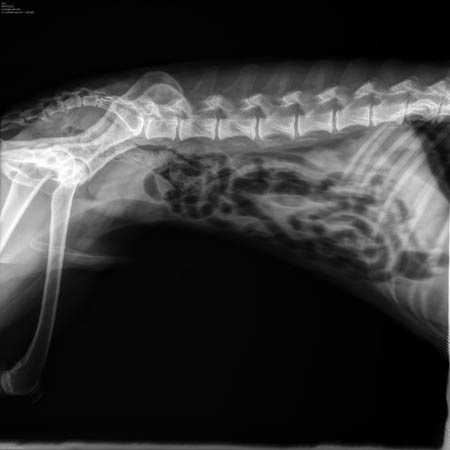

![]() In de lage rug zijn geen problemen zichtbaar |